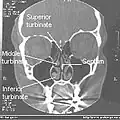

Normal Nose CT Front cross section -

Coronal section of nasal cavities -